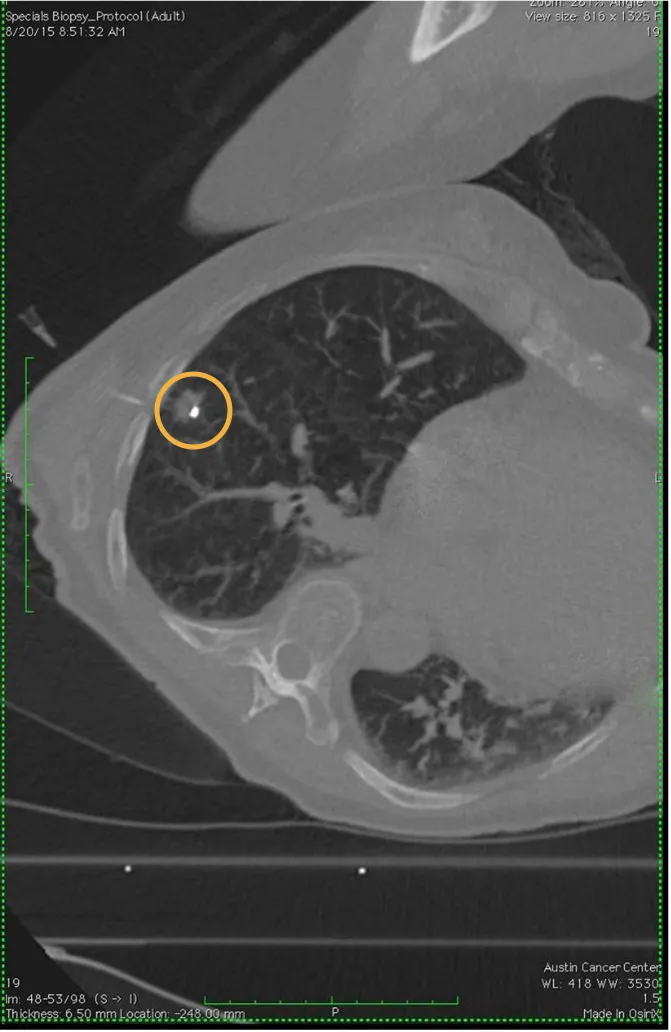

Gold Anchor for marking lung nodules prior to surgery

Lung nodules can be challenging to locate intraoperatively, especially if they are small, deep within the lung, or not visible on the lung surface.

Placing fiducial markers near or within the nodules before surgery (often guided by CT or bronchoscopy) has proven to be safe and effective and with a low failure rate for surgical localization1.

To our knowledge, Gold Anchor is the only fiducial marker pre-loaded in ultrathin 25G spinal needles. These thin needles have been proven safe for transthoracic biopsies, with a very low rate of pneumothorax. See our folder for more information on safety of thin needles.

Gold Anchor implanted in lung tumor.